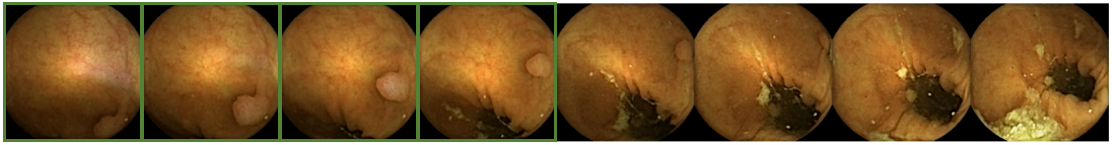

CAM visualization was applied to the output of the network. This method generates a heat map, where the red tones show the regions of the image that obtain a high response from the filters. Figure 9 shows in the first row eight polyps frames where the different morphology and size of the polyps may be observed. In the second row, the CAM visualization method highlights the location where the system focused to predict that there was a polyp.

Figure 11 shows eight polyp images where the system has not obtained enough features to predict the frame as polyp. Each image shows a boundary with the location of the polyps. These difficult cases are complex to detect in single images by the system. The evaluation of a whole sequence of images where the polyp is seen facilitates detection by the human eye. Due to the complexity of polyp detection, sometimes is easier for humans to detect them through the sequence.

Figure 12 shows the second sequence of images in Figure 1 with the output of the system represented by adding a green square around the frames where the system has detected a polyp. Although in this example the system missed two frames where the polyp is present, the detection in four frames is sufficient for the physician to establish the diagnosis.